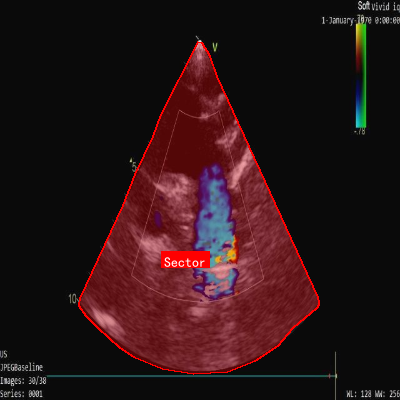

echo_info_sector数据集是一个专注于超声心动图图像中扇形区域检测的数据集,由qunshankj用户提供并采用CC BY 4.0许可证授权。该数据集于2023年3月14日创建,包含646张经过预处理的超声心动图图像,所有图像均被调整为640x640像素的统一尺寸。数据集中的扇形区域采用YOLOv8格式进行标注,仅包含一个类别'Sector'。为增强数据集的多样性和鲁棒性,研究人员对每张原始图像应用了多种数据增强技术,包括随机亮度调整(-25%至+25%)、随机高斯模糊(0至2像素)以及2%像素的椒盐噪声。数据集已按照标准划分为训练集、验证集和测试集三个部分,适用于计算机视觉领域中目标检测模型的训练与评估,特别是针对医学超声图像中特定解剖结构的自动识别任务。

超声心动图是心脏病诊断的重要工具,但手动分析耗时且容易漏诊。今天,我们要分享一个基于YOLOv10n-CSP-PTB的超声心动图扇形区域智能检测方案,这个方法不仅能自动识别心脏结构,还能显著提升诊断效率!🚀

YOLOv10作为最新的目标检测模型,在保持高效性的同时大幅提升了精度。结合CSP-PTB(Cross Stage Partial Path Through Block)架构,特别适合医疗图像的精细检测任务。本文将带你一步步实现超声心动图扇形区域的智能检测,从环境搭建到模型部署全流程讲解!🔬

超声心动图分析面临诸多挑战:图像质量不稳定、解剖结构复杂、扇形区域边界模糊等。传统方法依赖医生经验,主观性强且效率低下。基于深度学习的目标检测为这些问题提供了新的解决方案。